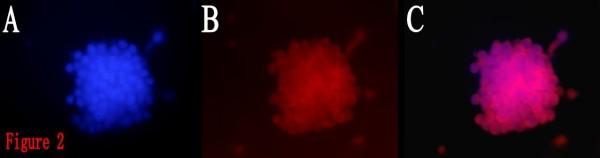

Limiting dilution and clonogenic assay were used to isolate and screen BTSCs from the fresh specimen of human brain glioblastoma. The obtained BTSCs, which were cultured in serum-free medium, were classified into four groups in accordance with the composition of the different treatments. The proliferation of the BTSCs was evaluated by MTT assay. The BTSCs were induced to differentiate in serum-containing medium, and classified into the ATRA group and control group. On the 10th day of induction, the expressions of CD133 and glial fibrillary acidic protein (GFAP) in the differentiated BTSCs were detected by immunofluorescence. The differentiated BTSCs were cultured in serum-free medium, the percentage and the time required for formation of brain tumor spheres (BTS) were observed.

BTSCs obtained by limiting dilution were all identified as CD133-positive by immunofluorescence. In serum-free medium, the proliferation of BTSCs in the ATRA group was observed significantly faster than that in the control group, but slower than that in the growth factor group and ATRA/growth factor group, and the size of the BTS in the ATRA group was smaller than that in the latter two groups(P < 0.01). In serum-containing medium, the expression percentages of CD133 and GFAP in the differentiated BTSCs were (2.29% +/- 0.27%) and (75.60% +/- 4.03%) respectively in the ATRA group, and (7.05% +/- 0.49%) and (12.51% +/- 0.77%) respectively in the control group. The differentiation rate of BTSCs in the ATRA group was significantly higher than that in the control group (P < 0.05), but there was still CD133 expressed in the ATRA group. The differentiated BTSCs could re-form BTSs in serum-free medium. The percentage of BTS formation in the ATRA group was(4.84% +/- 0.32%), significantly lower than that in the control group (17.71% +/- 0.78%) (P < 0.05), and the time required for BTS formation in the ATRA group was (10.07 +/- 1.03)d, significantly longer than that in the control group (4.08 +/- 0.35)d (P < 0.05).

通过有限稀释获得的 BTSCs 均通过免疫荧光鉴定为 CD133 阳性。在无血清培养基中,ATRA 组 BTSCs 的增殖速度明显快于对照组,但慢于生长因子组和 ATRA/生长因子组,ATRA 组的 BTS 体积小于后两组(P < 0.01)。在含血清培养基中,ATRA 组分化后的 BTSCs 中 CD133 和 GFAP 的表达百分比分别为(2.29% ± 0.27%)和(75.60% ± 4.03%),对照组分别为(7.05% ± 0.49%)和(12.51% ± 0.77%)。ATRA 组 BTSCs 的分化率明显高于对照组(P < 0.05),但 ATRA 组仍有 CD133 表达。分化后的 BTSCs 可在无血清培养基中重新形成 BTS。ATRA 组 BTS 形成的比例为(4.84% ± 0.32%),明显低于对照组的(17.71% ± 0.78%)(P < 0.05),ATRA 组形成 BTS 的时间为(10.07 ± 1.03)d,明显长于对照组的(4.08 ± 0.35)d(P < 0.05)。